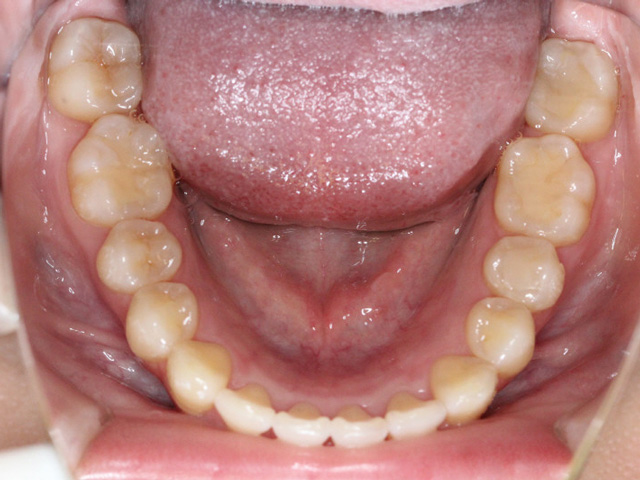

小児矯正とは、主に成長期にある子どもを対象に行う歯科矯正治療のことを指します。

永久歯がすべて生え揃ってから行う大人の矯正とは異なり、顎の成長をコントロールしながら、歯が正しく並ぶための土台を整えていくのが特徴です。

そのため、小児矯正では歯列不正(歯並びが悪い状態)を効率良く歯を動かすことが可能で、装置の選択が適切であれば、短い期間で歯並びを改善させることができます。

歯並びを改善させるだけでなく、それと同時に生え変わっていない永久歯が、将来並ぶスペースを確保したり、上下の顎のバランスを整えたりします。

多くの歯並びの問題は、歯そのものが悪いのではなく、顎の大きさが不足していることが原因で起こります。

例えば、顎が小さいと、永久歯が生えるスペースが足りず、歯が重なったり、外に押し出されたりします。これを無理に並べようとすると、大人の矯正では抜歯が必要になることもあります。しかし、成長期に顎の幅を広げておけば、そもそも抜歯をしなくても済む可能性が高くなるのです。小児矯正では、装置を使って顎の成長方向を誘導したり、舌や唇の使い方、呼吸の仕方といった口周りの癖を改善することもあります。これらは歯並びに大きな影響を与える要素であり、見過ごされがちですが非常に重要です。